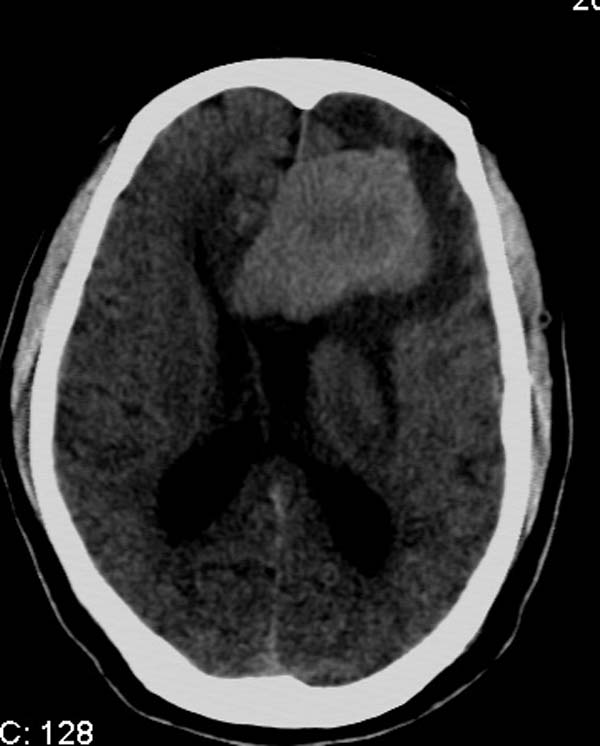

以下是引用拾荒者在2007-10-5 19:31:00的发言:[br]左额叶镰旁不规则形高密度影,中间见钙化灶及略低密度影,占位征象明显,周围有低密度水肿带环绕,首先考虑脑膜瘤。